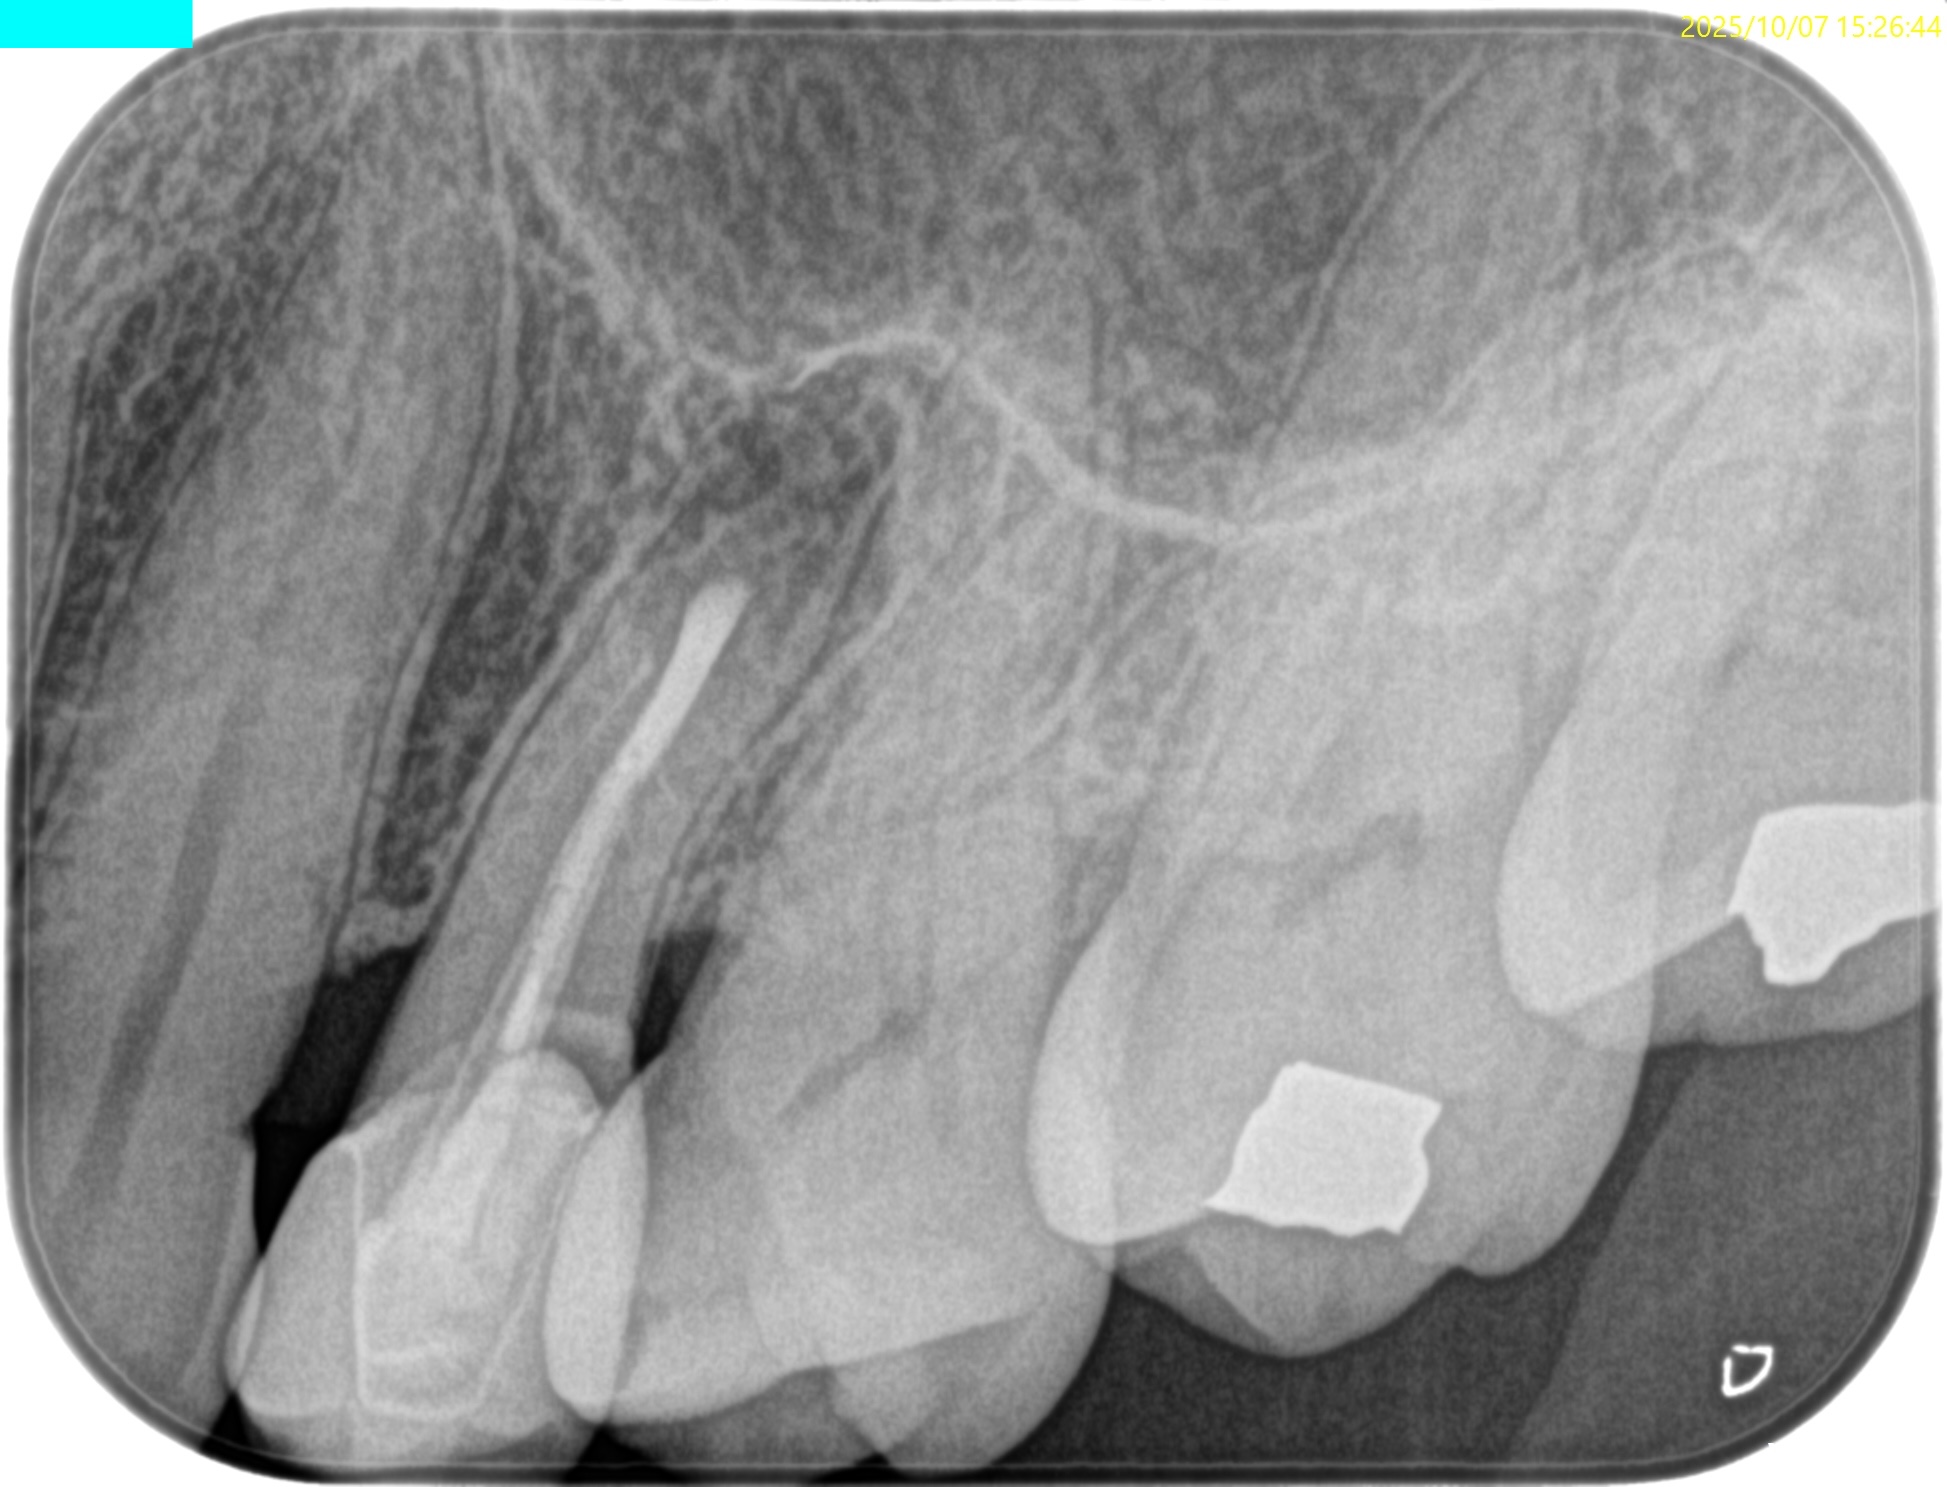

PA(2025.8.22)

もの詰まりはこの#13の遠心の築造体が剥き出しのマイクロリーケージであろう。

CBCT(2025.8.22)

#13 遠心のマージンが歯肉縁下でクラウンが不適合だ。ここにものが詰まるようだ。

これが患者さんの主訴である。

また、根尖病変があり根管形成・根管充填が太くなされていることからApicoectomyへ移行することになった。